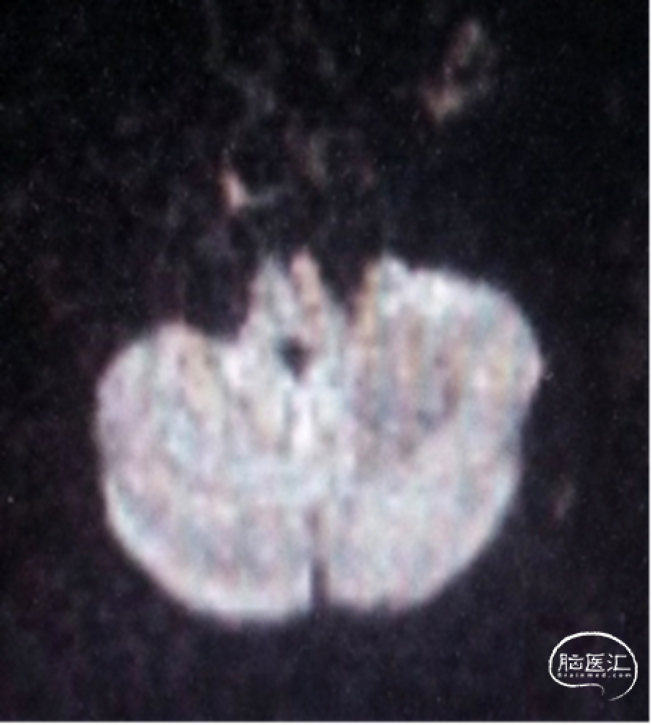

术后MRI未见新发脑梗,无新发神经系统阳性体征